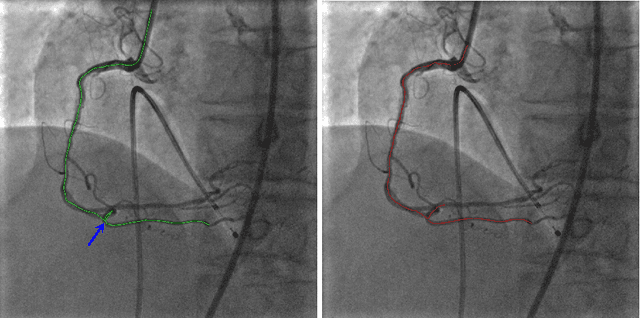

Abstract:In this article, we present the work towards improving the overall workflow of the Percutaneous Coronary Interventions (PCI) procedures by capacitating the imaging instruments to precisely monitor the steps of the procedure. In the long term, such capabilities can be used to optimize the image acquisition to reduce the amount of dose or contrast media employed during the procedure. We present the automatic VOIDD algorithm to detect the vessel of intervention which is going to be treated during the procedure by combining information from the vessel image with contrast agent injection and images acquired during guidewire tip navigation. Due to the robust guidewire tip segmentation method, this algorithm is also able to automatically detect the sequence corresponding to guidewire navigation. We present an evaluation methodology which characterizes the correctness of the guide wire tip detection and correct identification of the vessel navigated during the procedure. On a dataset of 2213 images from 8 sequences of 4 patients, VOIDD identifies vessel-of-intervention with accuracy in the range of 88% or above and absence of tip with accuracy in range of 98% or above depending on the test case.